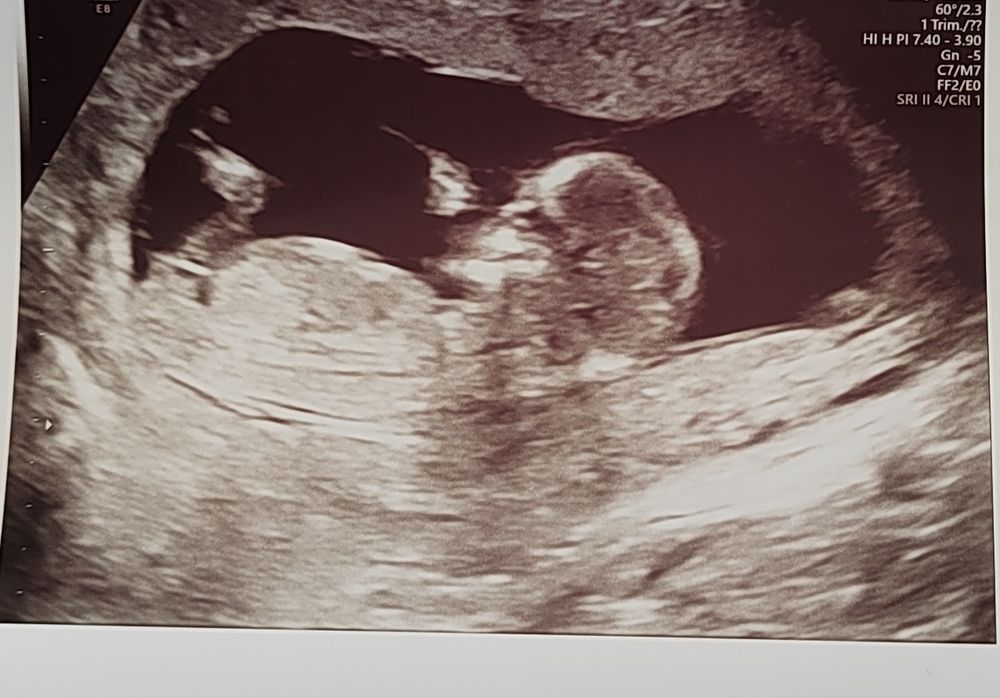

Арина, какой-то очень большой и четкий бугорок😄я думала жто что-то другое

Арина, да, с этим фото очень похоже

Юлия, по 1 фото сказала бы мальчик, по последней девочка 😁 У нас очень Крутая узист в Кулакова, сказала с уверенностью уже в 12 недель, что парень ) но и добавила , что тут ярко выраженный половой синус 🤣Нипт подтвердил. У некоторых деток и ко 2 скринингу сложно сказать, но по идее уже можно. Главное , чтобы здоровенький малыш был 😊

Юлия, если по градусам смотреть, то примерно девочка будет. На мальчика не похоже. Это если по градусам судить

Юлия, у меня первая мысль была что девочка. Но я совсем в этом не разбираюсь. Мне кажется на некоторых снимах ножками закрыто🤭